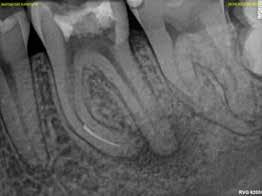

Mind a periapicalis röntgenfelvétel, mind a CBCT-felvétel igazolta, hogy a fragmentum mélyen a gyökércsatorna görbülete mögött, az apikális harmadban helyezkedik el a mesiobuccalis csatornában, valahol a mesiolingualis csatornával történő egyesülés után. Ezenfelül mind a mesialis, mind a distalis gyökércsúcs körül periapicalis gyulladás jelei voltak megfigyelhetőek (1–3. ábra). A betört eszköz nagyjából 5 mm-es hosszúsággal rendelkezett. A mesiolingualis csatornán keresztül a betört fragmentum mellett történő további gyökércsatorna-megmunkálást kockázatosnak ítéltük, mivel nagy esélyt láttunk rá, hogy így a másik eszköz is eltörik, amely pedig a gyökértömés elkészítését nehezítette volna. Azonban a SWEEPS technológiának és a biokerámia sealereknek köszönhetően más megoldási lehetőségek is nyitva álltak előttünk.

ábra: Kiindulási röntgen. A felvételen jól látható a betört eszköz és a periapikális lézió.

2. ábra: Kiindulási CBCT-felvétel. A betört eszköz mélyen a gyökércsatorna görbülete mögött található.

3. ábra: A betört eszköz vége jóval a mesiobuccalis és mesiolinguális csatorna egyesülésének pontja alatt helyezkedik el.